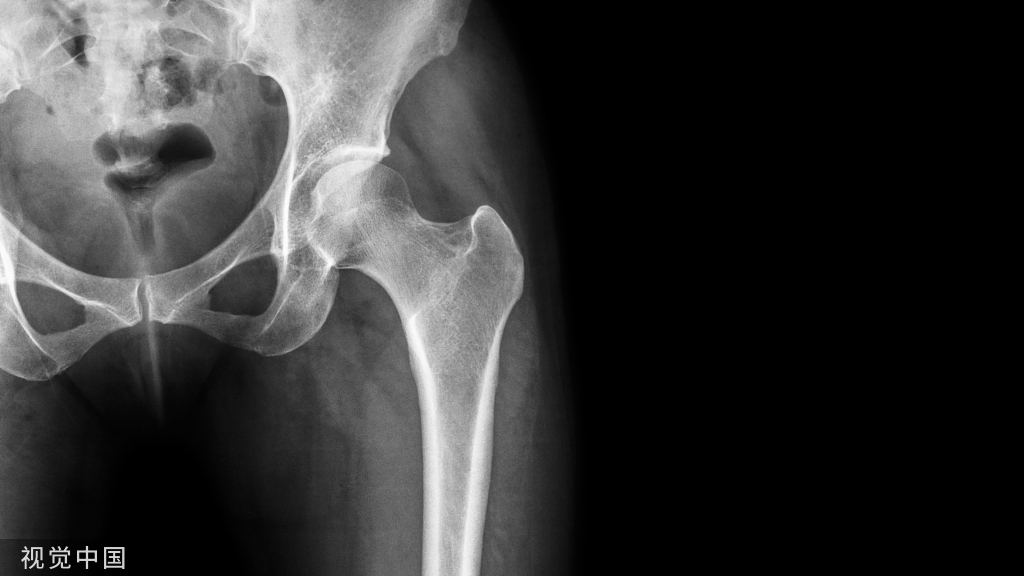

指包括肱骨外科颈在内及其以上部位的骨折,根据ham方格理论我们可以对肱骨近端进行定义。

解剖颈、外科颈、大结节、小结节、还要记得肱骨头的35-40度的后倾角度、130度左右的颈干角、大结节低于肱骨头大约8mm。

常用的X线检查主要有3个位置:正位、Y位、腋位